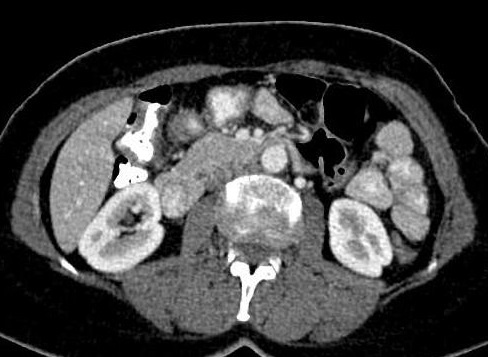

Sur les coupe TDM axilae a travers le

choix pour diagnostic les anormalie du pancreas |